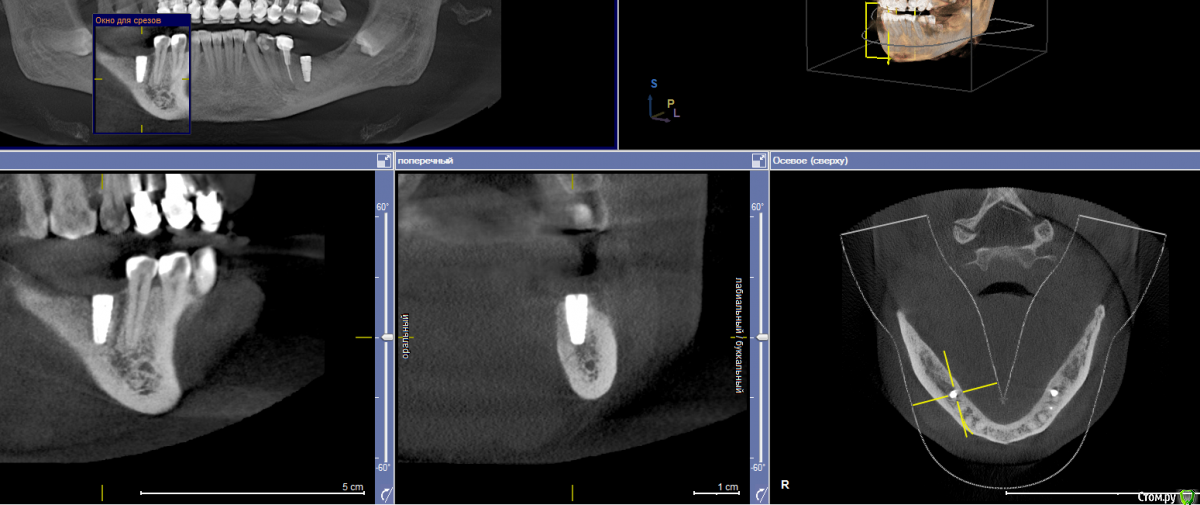

Малик Опубликовано 18 мая, 2016 Поделиться Опубликовано 18 мая, 2016 (изменено) Ровно 3 месяца назад произведена установка имплантата 4.6 с НКР. Заживление первичным натяжением, на момент снятия швов все идеально (К сожалению, нет фоток, не обзавелся еще фотоаппаратом). 2 дня назад позвонила пациентка и сказала, что прям по вершине гребня появилось какое-то образование мягкой консистенции, была назначена на сегодня. Позвонила вчера вечером с жалобой, что данное образование лопнуло, и появилась сукровица. На осмотре определяется свищ по вершине гребня и язычно.Посоветуйте какую тактику предпринять? Раскрыть и поставить формик? И у кого какие мнения по поводу причины этого всего? кт с имплантатом было сделано сегодняP.S. извиняюсь за очень низкое качество фотографий. Изменено 18 мая, 2016 пользователем Малик Ссылка на комментарий

TIGER Опубликовано 19 мая, 2016 Поделиться Опубликовано 19 мая, 2016 Формик с ССТ.Там пришеечная резорбция Ссылка на комментарий

Малик Опубликовано 19 мая, 2016 Автор Поделиться Опубликовано 19 мая, 2016 Я к тому что имплантат был установлен супракрестально,на 1,5мм ( зона лазер лок) выше гребня. Ссылка на комментарий

TIGER Опубликовано 20 мая, 2016 Поделиться Опубликовано 20 мая, 2016 Я к тому что имплантат был установлен супракрестально,на 1,5мм ( зона лазер лок) выше гребня.в этом вся причина...зачем не до глубляли? Ссылка на комментарий